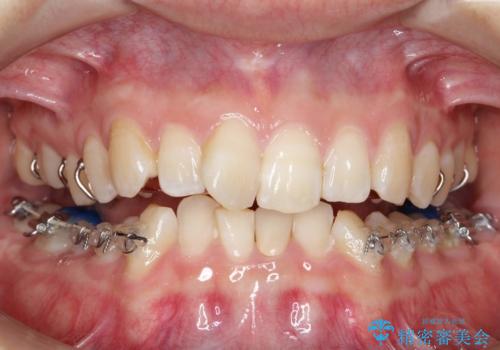

ハーフリンガル ワイヤー矯正による非抜歯・過蓋咬合の治療

- 審美装置

- 3年

- 非抜歯、大臼歯遠心移動による臼歯関係の是正・過蓋の改善をハーフリンガル・ワイヤー矯正にて計画した。

しかし、諸々の理由でマウスピース矯正をおこなえない場合、本例のようにワイヤーを用いて治療することも可能ですが、そもそも装置が歯につかないため、非常に大変な労力を費やすことになります。